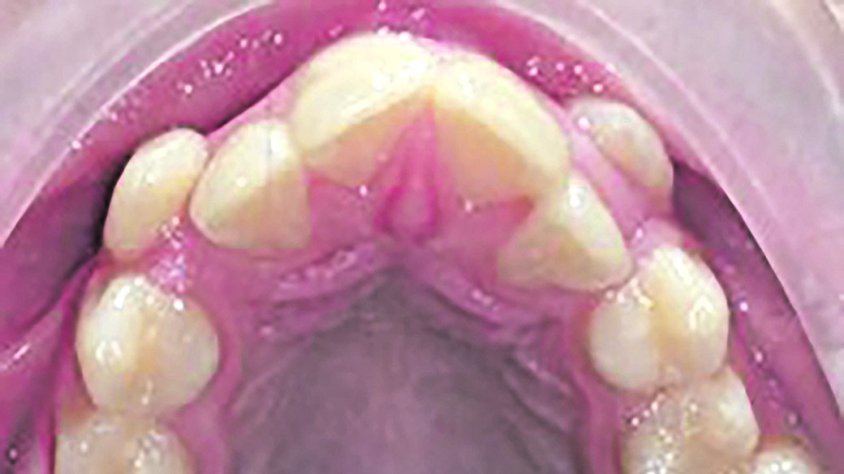

Hi ha estudis on s’evidencia com amb una dieta primitiva hi ha un bon desenvolupament cranial, de les arcades dentals, bona condició física i immunitat als processos degeneratius moderns com l’artritis, malalties cardíaques i afeccions internes. En aquest mateix estudi es veu com els fills d’aquestes poblacions que canvien d’hàbits dietètics i d’estil de vida perden aquesta immunitat, així com els empitjora el desenvolupament facial i la forma dels arcs dentals i augmenten les càries.